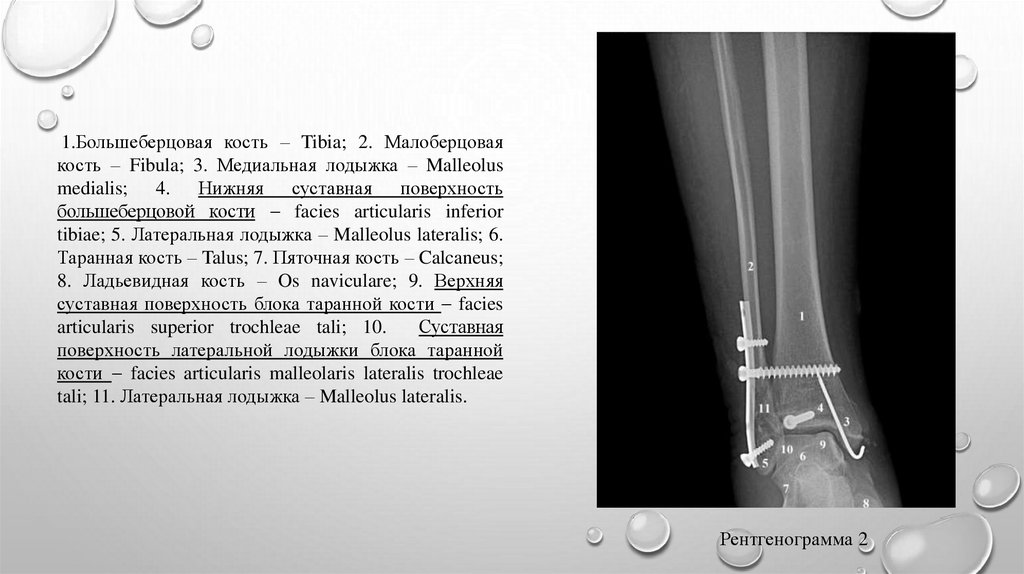

1.Большеберцовая кость – Tibia; 2. Малоберцовая

кость – Fibula; 3. Медиальная лодыжка – Malleolus

medialis; 4. Нижняя суставная поверхность

большеберцовой кости facies articularis inferior

tibiae; 5. Латеральная лодыжка – Malleolus lateralis; 6.

Таранная кость – Talus; 7. Пяточная кость – Calcaneus;

8. Ладьевидная кость – Os naviculare; 9. Верхняя

суставная поверхность блока таранной кости facies

articularis superior trochleae tali; 10.

Суставная

поверхность латеральной лодыжки блока таранной

кости facies articularis malleolaris lateralis trochleae

tali; 11. Латеральная лодыжка – Malleolus lateralis.